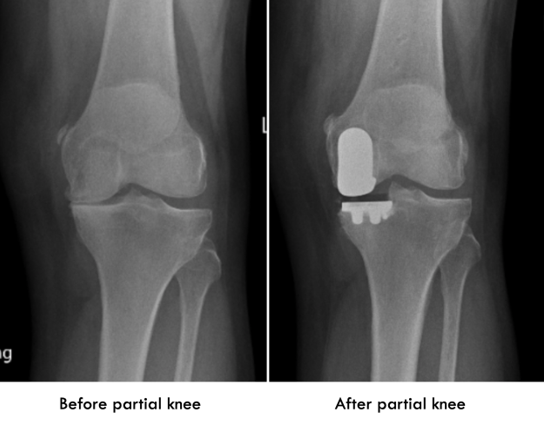

Unicompartmental or Partial Knee Replacement

Partial knee replacement is now one of our most commonly performed procedures. Rather than replacing the whole knee, partial knee replacement just ‘resurfaces’ the part that is suffering from arthritis. This confers the advantage of preserving most of the remainder of the knee including both cruciate ligaments. By leaving the rest of the knee untouched there is less bone loss and more preservation of sensation leaving it feeling more like your knee again.

In a large number of cases of knee arthritis the arthritis is only on the inside (‘medial side’) of the knee so why replace the whole knee?